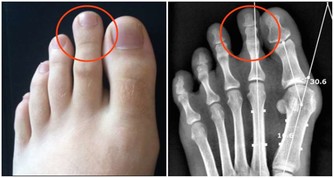

又有一位女士,因雙手發麻來診。按經絡上講,手指的哪一指發麻,應與相對應臟腑的功能失調有關,但兩隻手的手指全麻,病因就不一樣了,應該與頸椎椎體的錯位有關。於是,我按照整脊復位法,檢查她頸椎排列的形態。檢查頸椎排列時,發現頸椎第六椎椎體向右側凸起,凸出的這一椎體無疑是手指發麻的病因。根據發麻的病因,採用整脊復位的方法,將錯位的椎體復位,僅幾天的複位治療,錯位的椎體就復位了,結果發麻的手指變化不大。錯位的椎體已經歸位了,病症為什麼沒有大的好轉呢?

這說明對病因的判斷有誤。接著再次檢查病因,順著頸椎向下檢查胸椎時,發現胸椎的第一椎體向右凸出,胸椎第二椎體向左凸出,其他胸椎排列正常,在檢查胸椎中發現了新的情況。根據檢查出來的病因,採用整脊復位方法,對胸椎錯位的椎體進行複位,僅經過五天的複位治療,胸椎錯位的椎體復位了,兩手手指也不再發麻了。